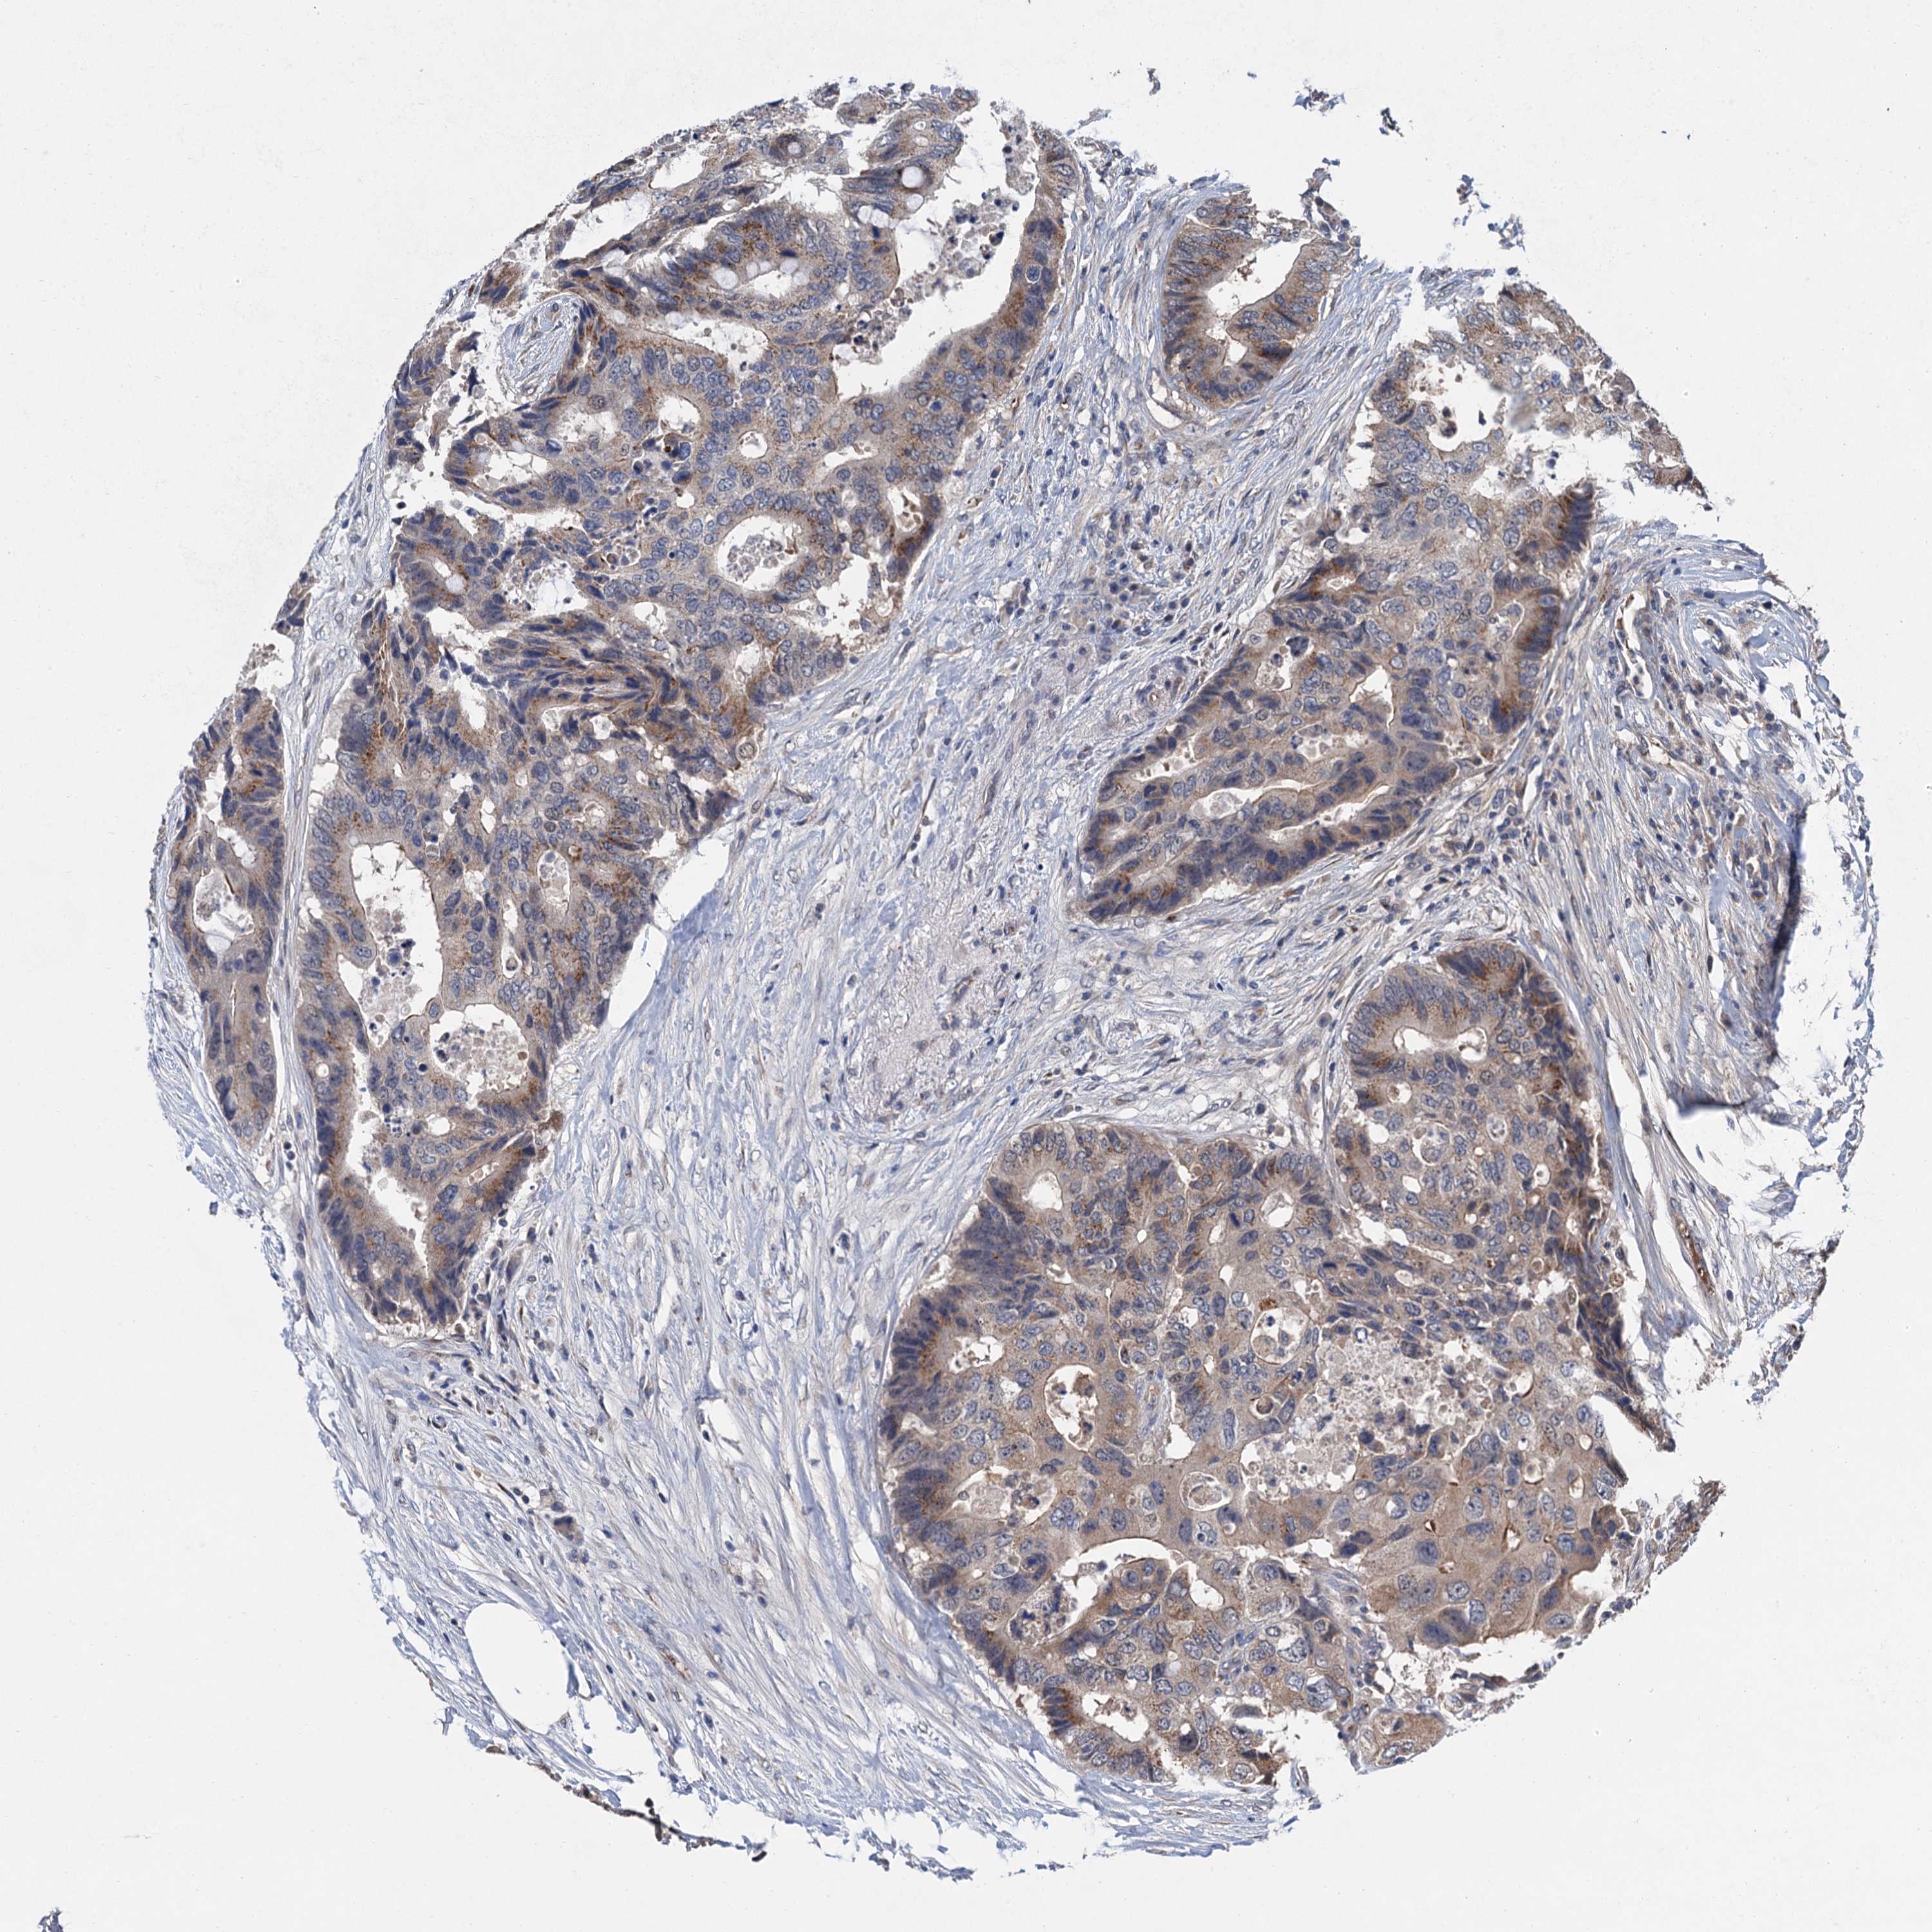

CANCER COLORECTAL CANCER Show tissue menu

Colorectal cancer

Human cancer

Colon adenocarcinoma